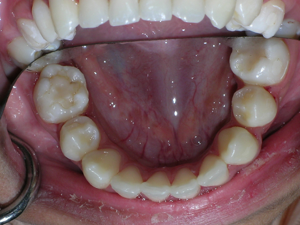

Here’s a young lady who presented with severe crowding. Often we think of crooked teeth as being limited to front teeth. Here one can see that back teeth can also get crowded. Braces were placed and select teeth were removed. Watch.

Here again we used a “Nance” holding arch. Look at some photos while the braces are on.